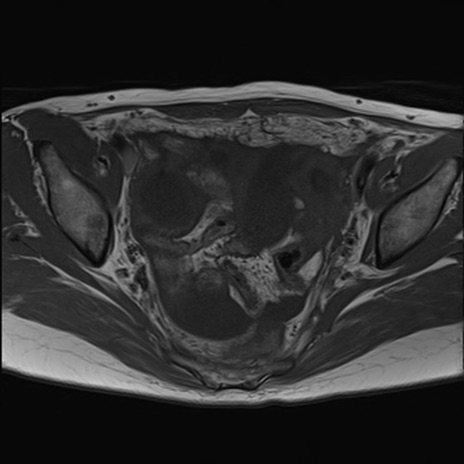

症例39 T1WI(横断像)

【症例】40歳代女性

【主訴】上下腹部痛

【現病歴】2日目から下腹部痛あり。夜間は痛みで眠れなかった。昨日より上腹部痛と下痢が出現。臥位で痛みは軽快したため、休んでいた。本日になって臥位でも立位でも痛みが強くなってきたため救急要請。

【既往歴】子宮内膜症

【身体所見】部:平坦・軟、左上下腹部に圧痛あり、反跳痛あり。

【データ】WBC 21800、CRP 26.78

MRI(4日後)